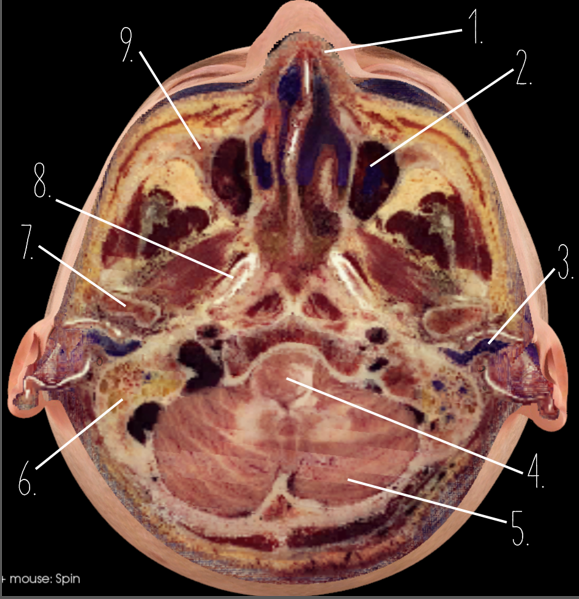

1?

Nasal Bone

2?

Maxillary Sinus

3?

External Acoustic Meatus

4?

Pons

5?

Cerebellum

6?

Mastoid Air Cells

7?

Mandibular Condyles

8?

Sphenoid Bone

9?

Maxillary Bone